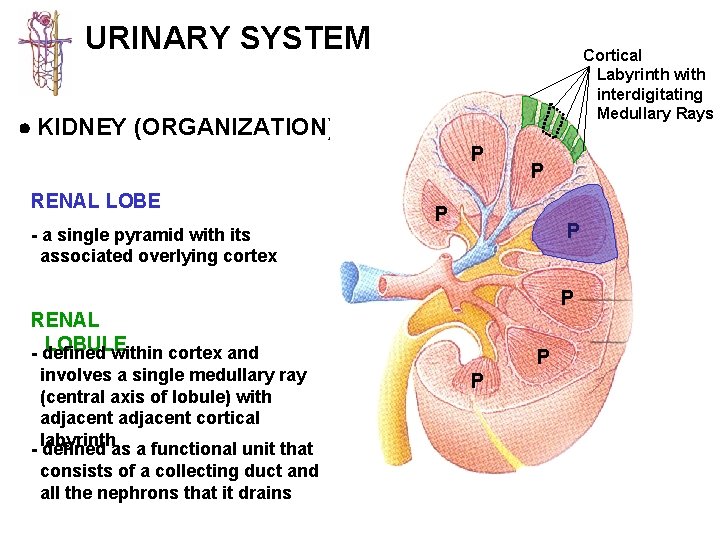

URINARY SYSTEM Cortical Labyrinth with interdigitating Medullary Rays KIDNEY (ORGANIZATION) P RENAL LOBE - a single pyramid with its associated overlying cortex P P P RENAL LOBULE - defined within cortex and involves a single medullary ray (central axis of lobule) with adjacent cortical labyrinth - defined as a functional unit that consists of a collecting duct and all the nephrons that it drains P P P